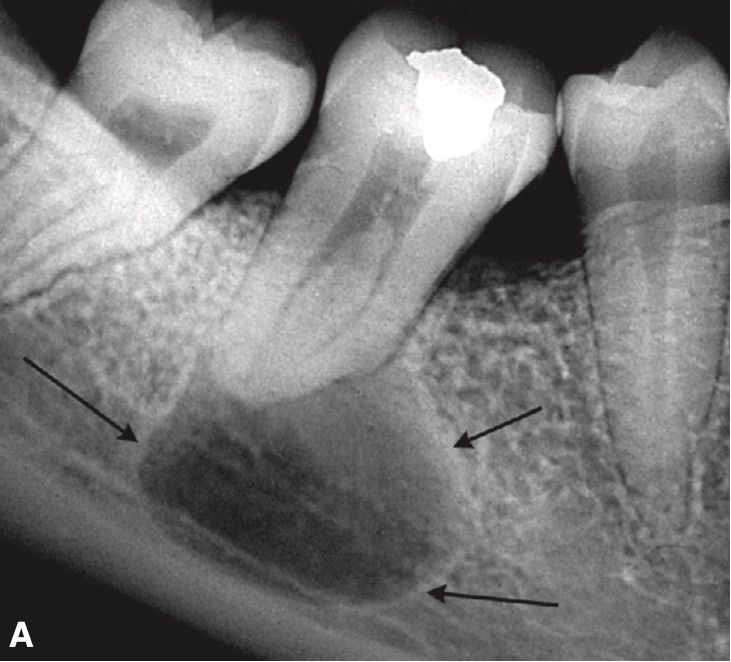

Представление клинического случая

Пациент, 26 лет, с бессимптомным анамнезом, поступил с отеком щечного вестибулярного аппарата и щечного пространства, связанным с большим периапикальным поражением вокруг вершин его нижнечелюстного моляра, №. 30 (рис. 1). Риски и преимущества эндодонтического лечения были изложены в дополнение к альтернативным методам лечения. Было получено информированное согласие.

Ортопантомография ( рис. 1 ) выявила большую периапикальную рентгенопрозрачность, около 4 см в горизонтальной плоскости и 3 см в вертикальной плоскости, связанную с зубами 21, 22, 23, 24 и, возможно, 25. Клиническое обследование выявило припухлость губ над этими зубов, болезненность при пальпации и перкуссии. Зубы 22, 23 и 24 не реагировали на термические и электрические тесты пульпы. Предварительный диагноз: радикулярная киста.Компьютерная томография (КТ) выявила поражение шириной около 4 см в переднезадней плоскости, поражающее всю правую межчелюстную кость и контактирующее с дном носа и верхнечелюстной пазухой ( Рис. 2 ). Отек, буккальный кортикальный разрыв и расширение кости были очевидны; эти особенности указывали на то, что поражение было доброкачественным.

Рисунок 1 : Панорамная рентгенограмма пациента с большим периапикальным поражением вокруг левого центрального резца верхней челюсти.